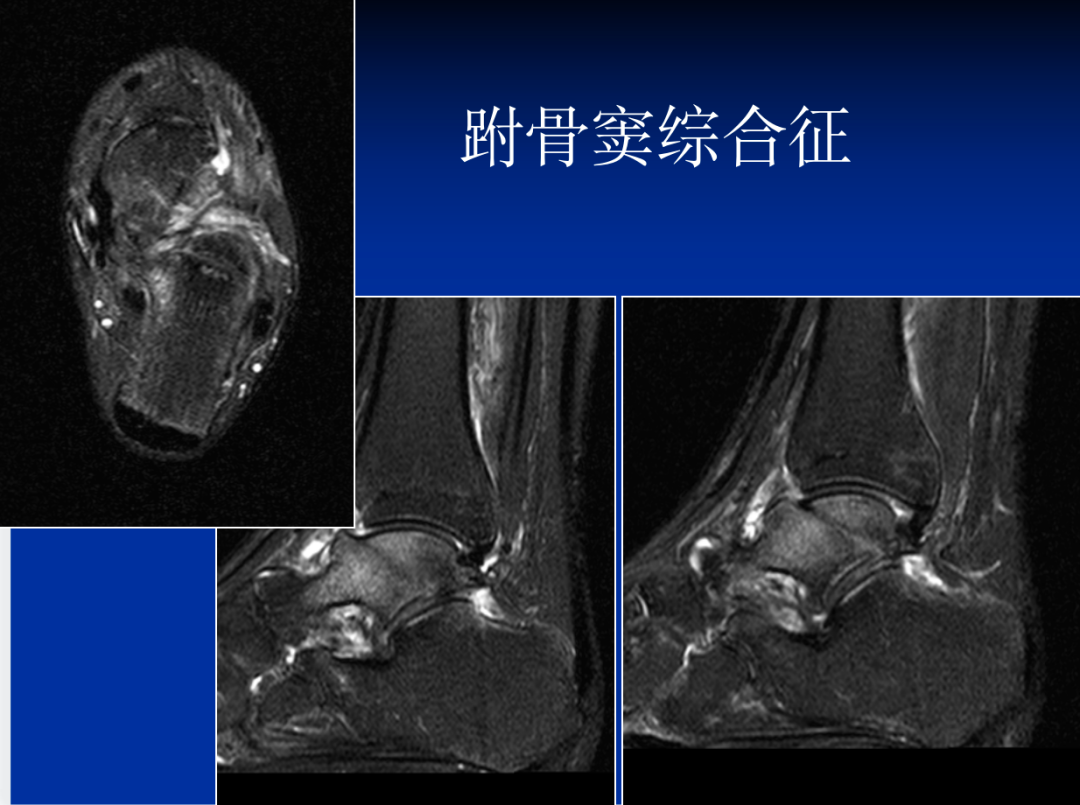

(八)跗骨窦综合征MRI检查

MRI检查适用于创伤后不明原因的持续性疼痛患者,有助于早期发现跗骨窦部位病理改变。正常跗骨窦在冠状位和矢状位MRlT1加权图像上显示高信号强度的脂肪和低信号强度的韧带组织,若跗骨窦脂肪为其他组织代替,T1、T2加权图像则均为广泛低信号强度改变,且可显示颈韧带和骨间韧带撕裂 。

跗骨窦综合征MRI诊断

异常表现:跗骨窦内软组织结构界限不清,水肿或纤维化,异常液体积聚,邻近的外侧韧带异常。病理基础为慢性滑膜炎,炎症,纤维化,滑膜囊肿。

跗骨窦综合征MRI表现

跗骨窦韧带撕裂,窦内结构模糊跗骨窦韧带纤维化(在T1WI和T2WI图像上呈低信号)

滑膜炎、液体和韧带扭伤(T1WI低信号;T2WI高信号)

在距下关节后面前、后微隐窝处的液性信号(T1WI低信号;T2WI高信号)

常见到踝外侧韧带撕裂,外踝肿胀